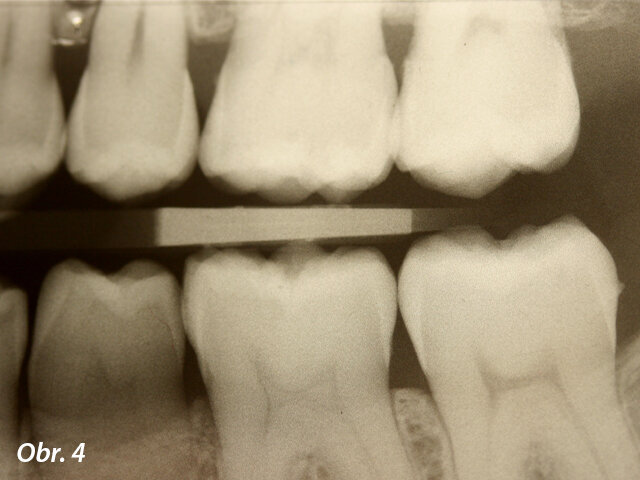

Kazuistika

Pacientka ve věku 38 let přišla do mé ordinace kvůli vyřešení zubních kazů. Při klinickém vyšetření nebyly patrné žádné kazy velkého rozsahu (obr. 1, 2). Až na RTG snímcích typu bitewing (obr. 3, 4), nezbytného prostředku pro diagnostiku v záchovné stomatologii, byly vidět mnohé kariézní léze, které zasahovaly do dentinových tkání. Pacientka požadovala vynikající estetický výsledek, což znamenalo sladění kompozitního materiálu se sklovinnými tkáněmi. Tento požadavek musel být zkombinován s funkční rehabilitací, která by v distálním úseku odolala zatížení žvýkacími silami a zajistila dlouhodobě minimální možné opotřebení. V rámci léčebného plánu bylo pacientce navrženo řešení v podobě přímého ošetření kazů v jednotlivých kvadrantech a nepřímé výplně v zubu 47, které by umožňovalo nejlepší přesnost okrajů a bylo zárukou dlouhodobě vynikajícího výsledku.